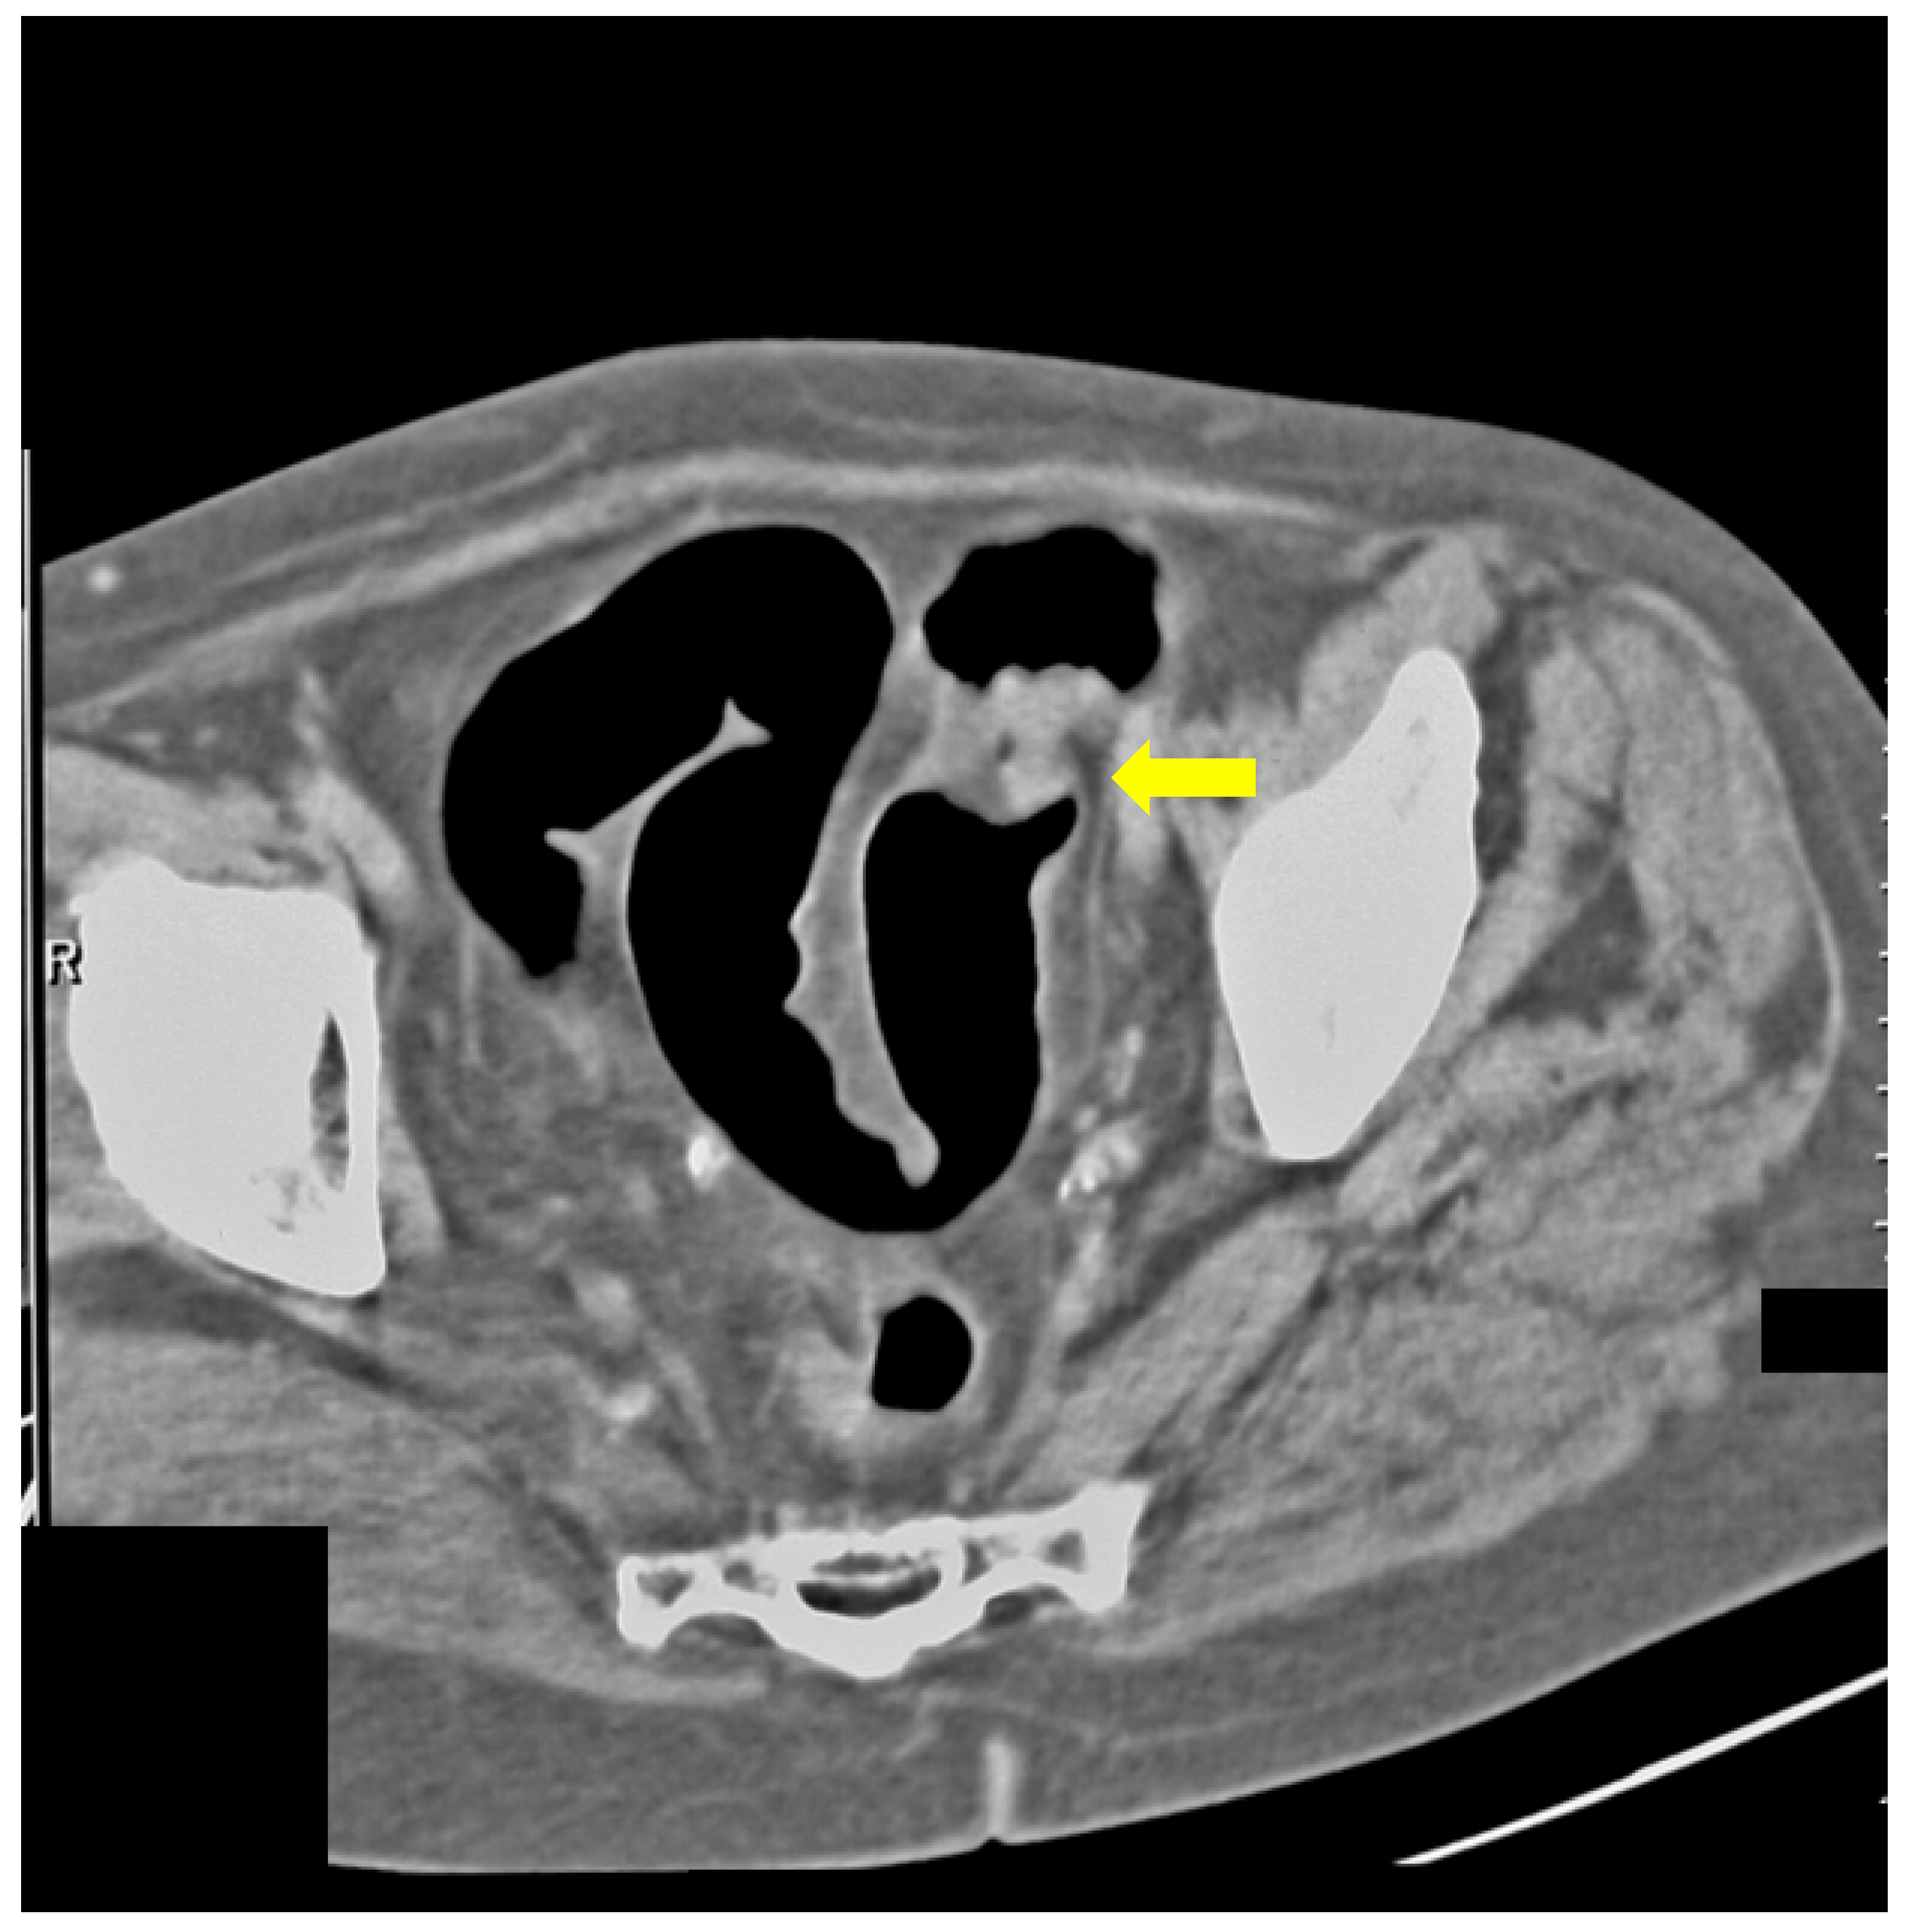

Additionally, we presented some of our patients in the group for which the virtual colonography was essential to establish the primary or other conditions. First, we presented a 73-year-old patient who had abdominal pain and constipation. The patient underwent incomplete FCS because of the stenosis of the lumen of the intestine (Figure 3). In this patient, we found tumor formation in the lumen of the colon, which arose from the intestinal wall and caused obstruction. The formation was with irregular margins and surrounded the intestine like a sleeve.

Figure 3.

CT colonography-axial scans in a supine position; 73-year-old patient with incomplete FCS due to intraluminal obturation of the sigmoid colon from carcinoma, which is presented in the figure as a tumor with soft tissue density (yellow arrow).